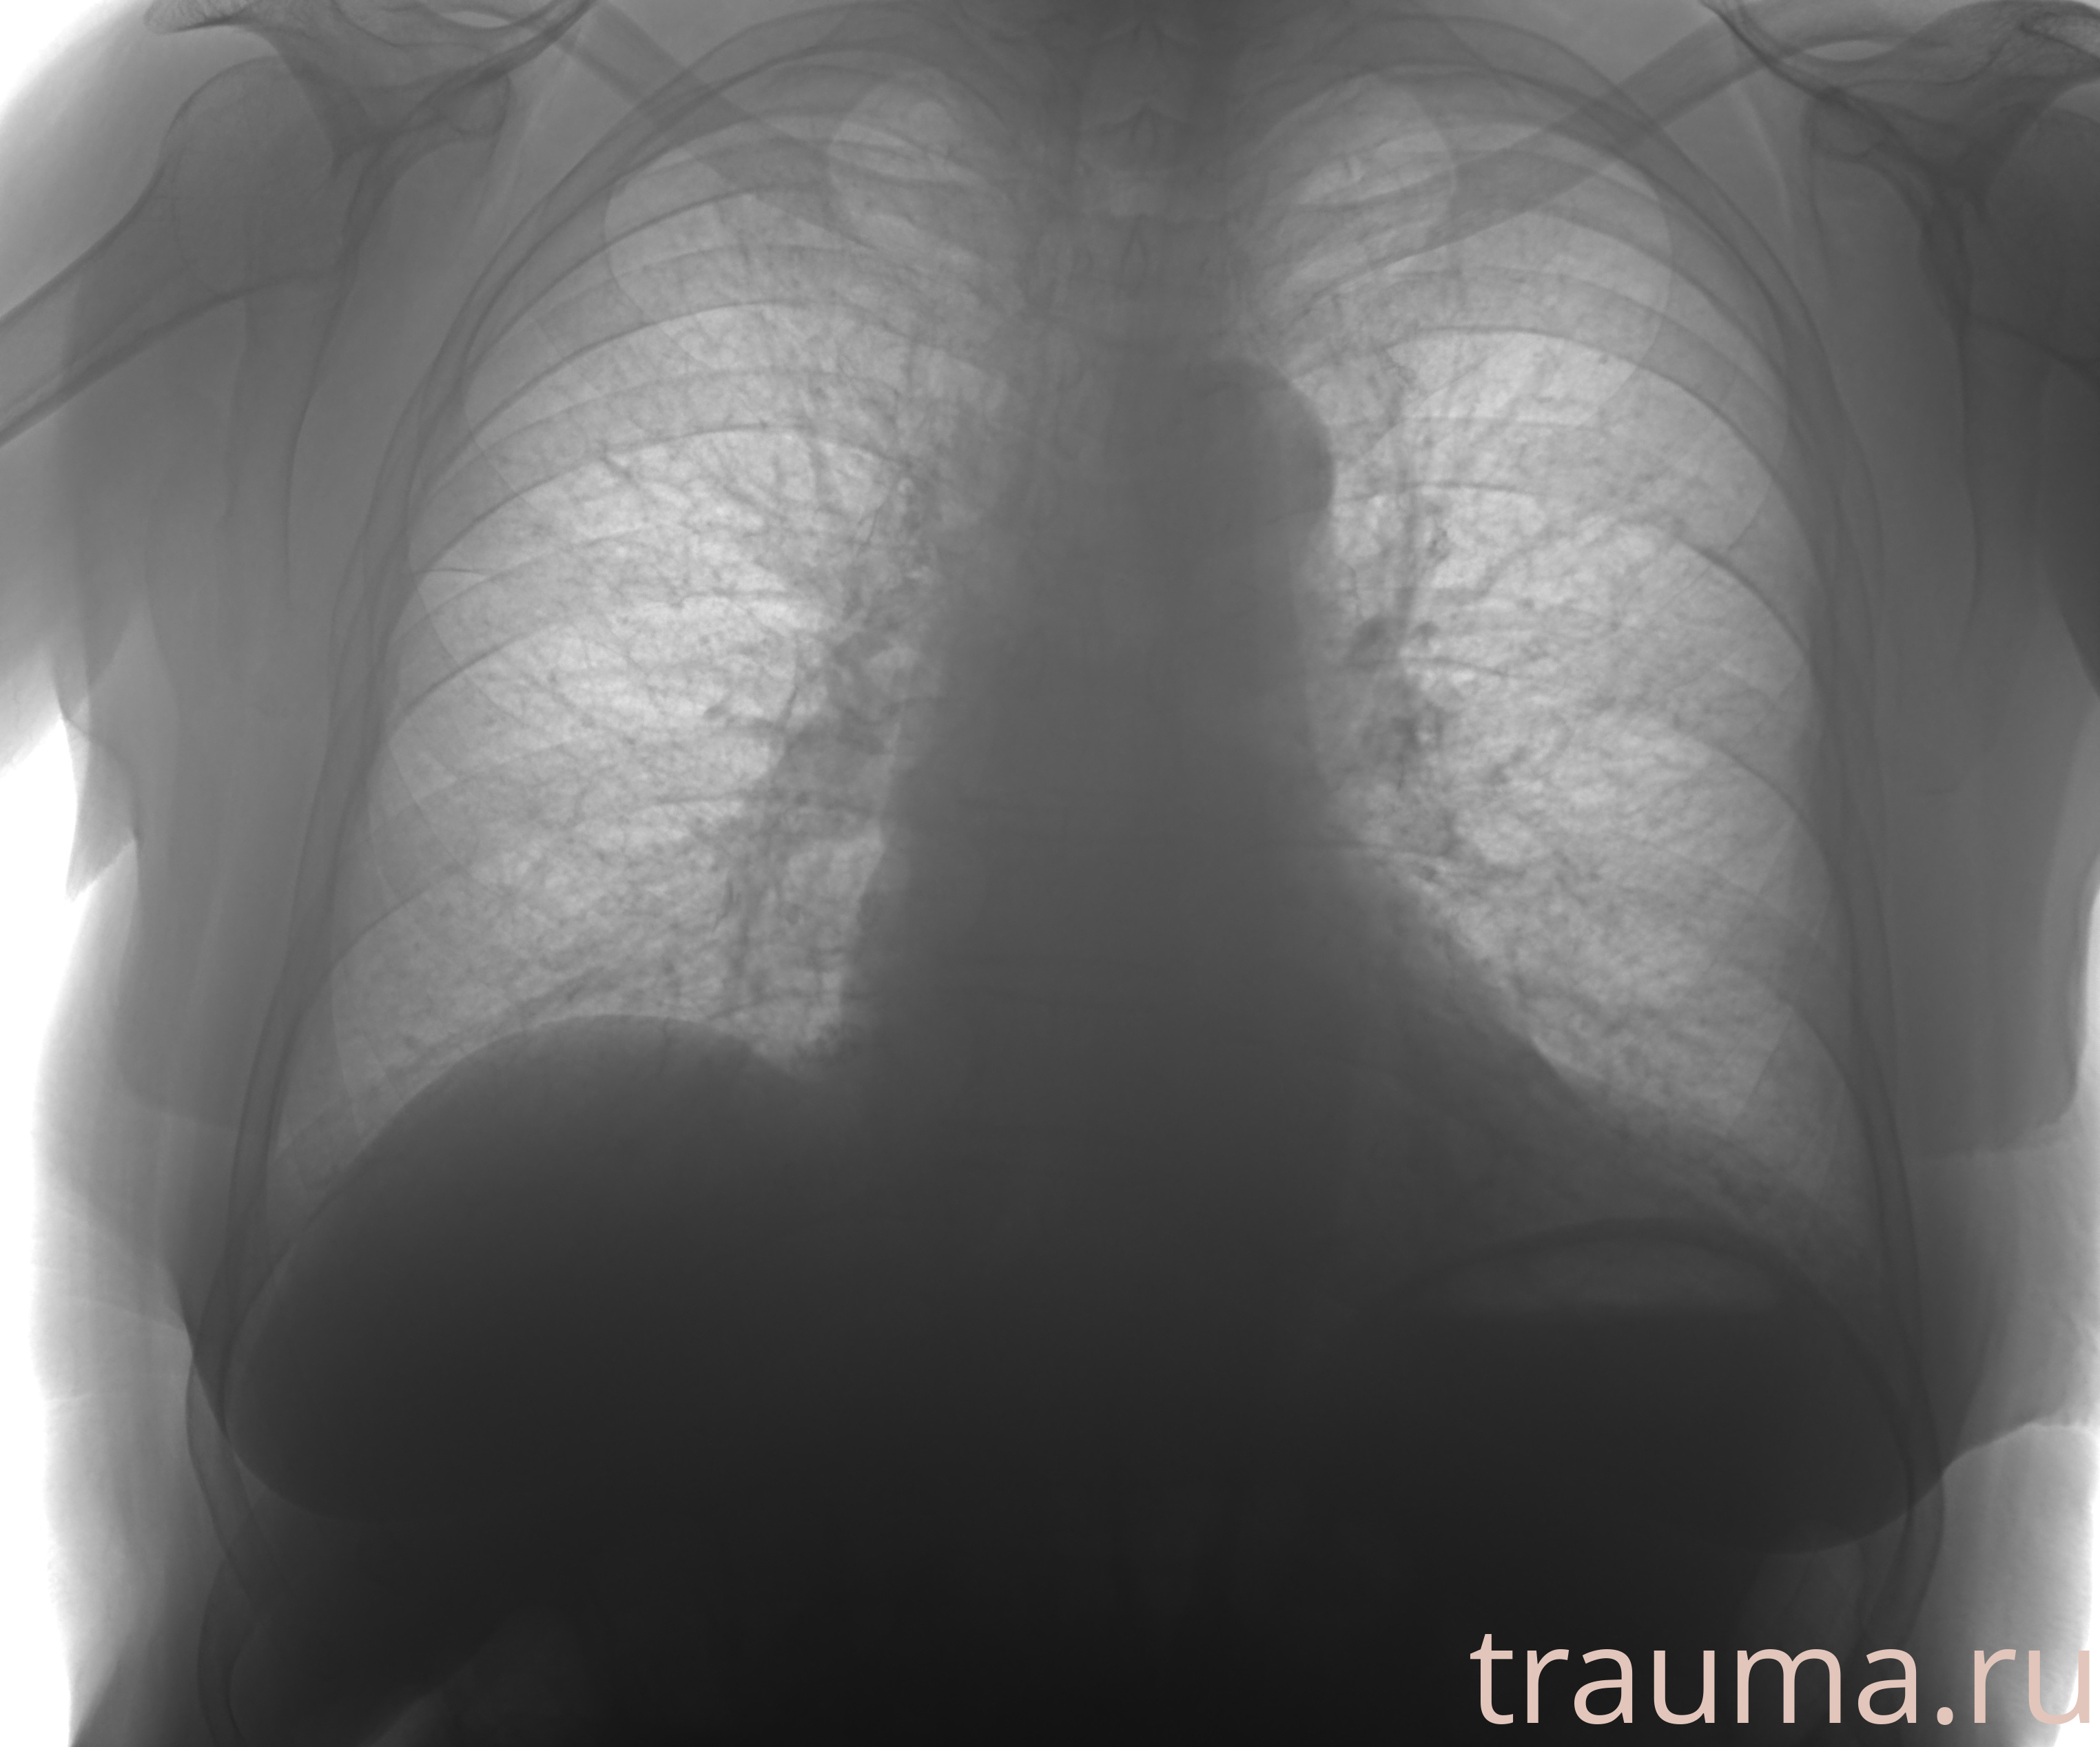

Рентгенограммы

Рентген на дому: по вашему адресу приезжает врач-рентгенолог, травматолог-ортопед с мобильным рентгеновским аппаратом, проводит диагностику травмы или заболевания, делает необходимые рентгенограммы, дает рекомендации по дальнейшему лечению. Получить качественные снимки в домашних условиях возможно благодаря уникальной методике, разработанной МосРентген Центром для института  Склифосовского

при переломе шейки бедра и пневмонии от компании МосРентген Центр - партнера Института имени Склифосовского